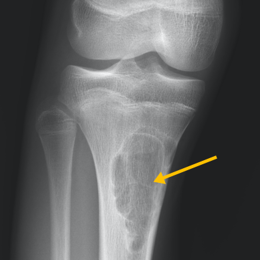

Radiographic imaging is used to help form a diagnosis. These include X-Ray, MRI, CT and Bone Scans

An example of a X-Ray and MRI are shown.